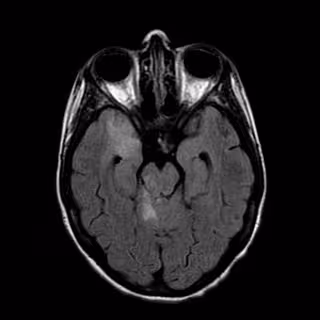

El tratamiento con ácido úrico mejora la recuperación de pacientes con ictus tratados con trombectomía mecánica, según un estudio presentado en el Congreso de la Organización Europea de Ictus (ESOC2016), que ha reunido a más de 3.500 especialistas en Barcelona y finaliza este jueves.

La Unidad de Ictus del Hospital Clínic ha liderado el estudio, que ha demostrado que este tratamiento, después de utilizar la trombectomía para destapar la arteria, mejora la recuperación funcional y la capacidad para realizar las actividades cotidianas de los pacientes y reduce las secuelas, ha explicado el hospital en un comunicado.

Se produce por una alteración de la circulación de la sangre al cerebro, y el tratamiento precoz es básico para conseguir que el paciente se recupere y minimizar sus secuelas; los ictus más comunes son los isquémicos (85%), por delante de las hemorragias cerebrales (15%).